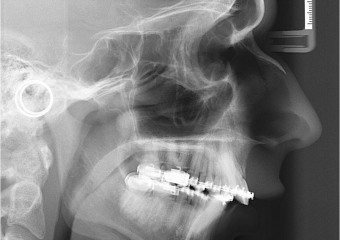

Telerradiografia inicial

Telerradiografia após a cirurgia